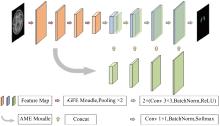

结合多尺度与注意力机制的脑组织分割方法

Brain tissue segmentation method combining multi-scale and attention mechanisms

针对脑皮层下组织部分结构(如纹状体)在医学影像中目标小、对比度低,图像分割难度大,在自动医学诊断中应用比较困难的问题,本文基于深度学习的方法提出了一种医学图像分割网络,在磁共振成像中分割组成纹状体的苍白球、尾状核、壳核3部分。本文提出的网络模型具有捕获全局和局部特征的能力,并建立了全局与局部信息的相关性,在深度不退化的同时有效融合不同尺度的深层语义特征和浅层细节特征,实现对纹状体的精确分割。模型在公开的脑部数据集上进行了验证,并与其他先进的方法进行对比,结果表明本文的戴斯相似系数、平均交并比、95%豪斯多夫距离分别为94.26%、90.94%、3.82,均优于其他几种方法,达到了先进水平,这表明本文模型可以提高对纹状体的分割精度,为相关疾病的研究提供依据。